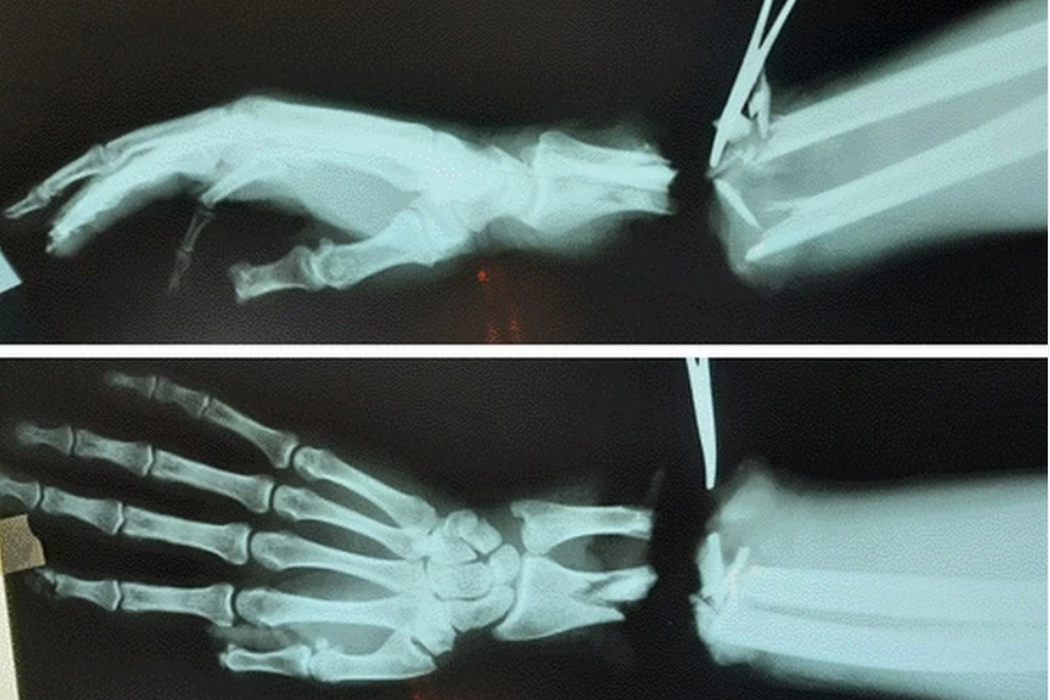

На рентгеновским снимках видно, что предплечье и кисть не связывало ничего, но врачи смогли их связать.

«Операция длилась семь часов с применением микроскопа, микрохирургических инструментов и шовного материала тоньше человеческого волоса», – повествуют кистевые специалисты из клиники.